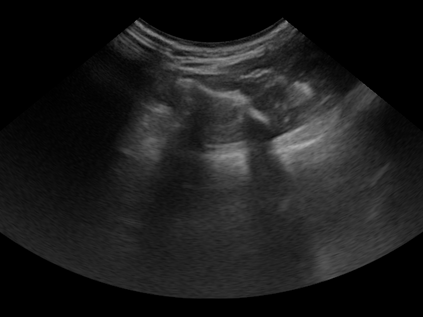

Three-dimensional (3D) freehand ultrasound (US) reconstruction without a tracker can be advantageous over its two-dimensional or tracked counterparts in many clinical applications. In this paper, we propose to estimate 3D spatial transformation between US frames from both past and future 2D images, using feed-forward and recurrent neural networks (RNNs). With the temporally available frames, a further multi-task learning algorithm is proposed to utilise a large number of auxiliary transformation-predicting tasks between them. Using more than 40,000 US frames acquired from 228 scans on 38 forearms of 19 volunteers in a volunteer study, the hold-out test performance is quantified by frame prediction accuracy, volume reconstruction overlap, accumulated tracking error and final drift, based on ground-truth from an optical tracker. The results show the importance of modelling the temporal-spatially correlated input frames as well as output transformations, with further improvement owing to additional past and/or future frames. The best performing model was associated with predicting transformation between moderately-spaced frames, with an interval of less than ten frames at 20 frames per second (fps). Little benefit was observed by adding frames more than one second away from the predicted transformation, with or without LSTM-based RNNs. Interestingly, with the proposed approach, explicit within-sequence loss that encourages consistency in composing transformations or minimises accumulated error may no longer be required. The implementation code and volunteer data will be made publicly available ensuring reproducibility and further research.